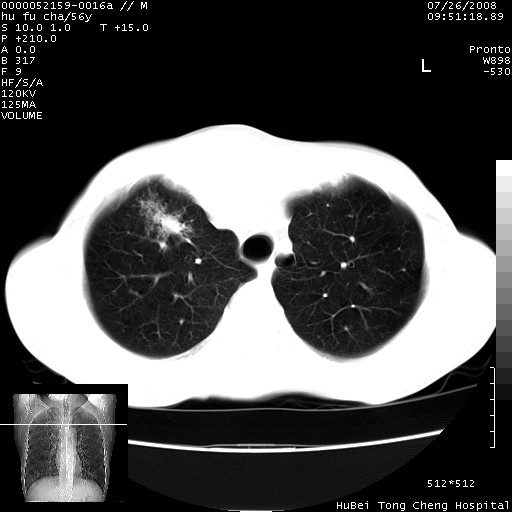

以下是引用zsl6918在2008-8-25 22:47:00的发言:[br]胸骨,胸椎及肋骨均可见多发转移表现,肝内低密度结节不除外转移。原发灶可能在右肺。双侧可见支扩表现。